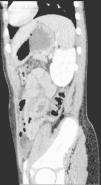

TCMD reconstrucción MPR sagital. Hallazgos: engrosamiento mural de un amplio segmento de intestino delgado (ileon) en el hemiabdomen izquierdo, que además asocia un aumento de realce parietal. Pequeña burbuja extraluminal, intraperitoneal, adyacente a la pared abdominal anterior en su vertiente izquierda. Los hallazgos son indicativos de perforación de intestino delgado.